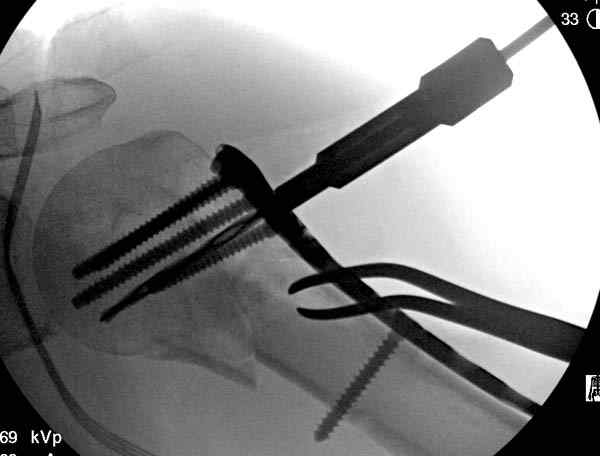

Здесь пример открытой репозиции 57 летнего с переломом плеча (1,2) смещение обнаружено на интероперационном снимке. При нормальной прямой проекция (3) угловое смещение обнаружили в аксиальной проекции (4)

После устранения смещения пластина установлена выше (5,6,7) и финальные снимки (8,9,10)